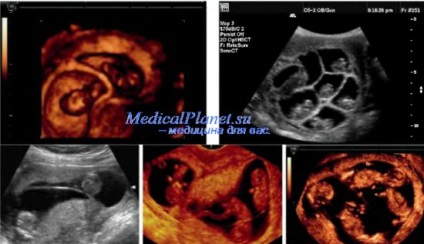

gemeni monozigoți. dizigoți.

Perinatală risc semnificativ mai mare de gemeni fetale a doua decât primul. Al doilea fruct al gemenilor de multe ori au nevoie de intubare, resuscitare, are un scor mai mic Apgar. morbiditate si mortalitate perinatala in timpul sarcinii monozygotic este de 2-3 ori mai mare decât la dizigoți. Acest lucru se datorează în primul rând la dezvoltarea sindromului de transfuzie feto-fetale. În plus, aproximativ 1% din sarcini sunt monoamniotic monochorionic monozigoți, pierderea perinatală care ajunge la 50%.

N. Sebire și colab. rezultatele perinatale, comparativ cu sarcina monochorionic si dichorionic. Ei au descoperit ca atunci cand gemenii monochorionic avortul până la 24 săptămâni a fost semnificativ mai mare - 12,2 și 1,8%, pierderea perinatală - 2,8 și 1,6%, incidența nașterilor premature, înainte de 32 de săptămâni - 9.2 și 5 , 5%, în greutate la naștere, ambele fructe sub percentila 5a - 7,5 și 1,7%. Frecventa de crestere discordant a fost similară cu sarcina monochorionic si dichorionic - 11,3 și 12,1%.